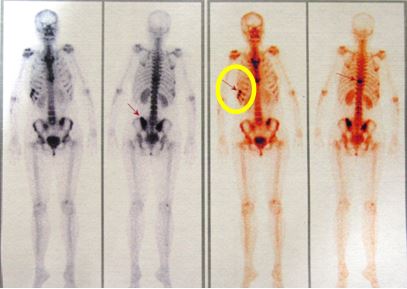

1. Chụp PET/CT sau điều trị 1 tháng:

Nhu mô hai phổi không thấy tổ chức hấp thu F-18 FDG bất thường, không thấy tràn dịch màng phổi.

- Hạch rốn phổi phải đường kính 0,9cm, tăng hấp thu F-18 FDG, max SUV=2,8.

- Xương chậu phải tăng hấp thu F-18 FDG, max SUV=6,17

Hình khuyết xương thân D10 không tăng hấp thu F-18 FDG

Hình 9: Hình ảnh PET/CT sau điều trị 1 tháng cho thấy hạch trung thất kích thước 0,9 cm tăng hấp thu F18-FDG với max SUV=2,8 (đầu mũi tên vàng), xương chậu phải tăng hấp thu F18-FDG với max SUV=6,17 (đầu mũi tên đỏ)

1. Xạ hình xương (sau 5 tháng điều trị): Tăng hoạt độ phóng xạ tại đốt sống ngực số 10, cung trước xương sườn 9,10; xương chậu bên trái (đầu mũi tên hình 11)

Hình 11: Xuất hiện thêm tổn thương xương sườn trên xạ hình xương (bệnh nhân bị va đập vào vùng mạn sườn phải do tai nạn trước khi làm xét nghiệm xạ hình xương)

Xạ hình xương trước điều trị: tăng hoạt độ phóng xạ (đầu mũi tên) tại đốt sống ngực 10 và khớp cùng chậu hai bên

Xạ hình xương sau điều trị: Tăng hoạt độ phóng xạ tại đốt sống ngực số 10, cung trước xương sườn 9,10; xương chậu bên trái (đầu mũi tên hình 11).

Hình ảnh tăng hoạt độ phóng xạ tại cung trước xương sườn 9,10 tương ứng với vị trí va đập trước khi làm xạ hình xương (vòng tròn vàng).